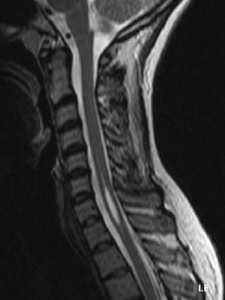

Syringomyélie Qu'est-ce que c'est ? La syringomyélie se caractérise par la formation d’une ou de plusieurs cavités à l’intérieur de la moelle épinière, pouvant causer des douleurs chroniques sévères, des troubles neurologiques ...